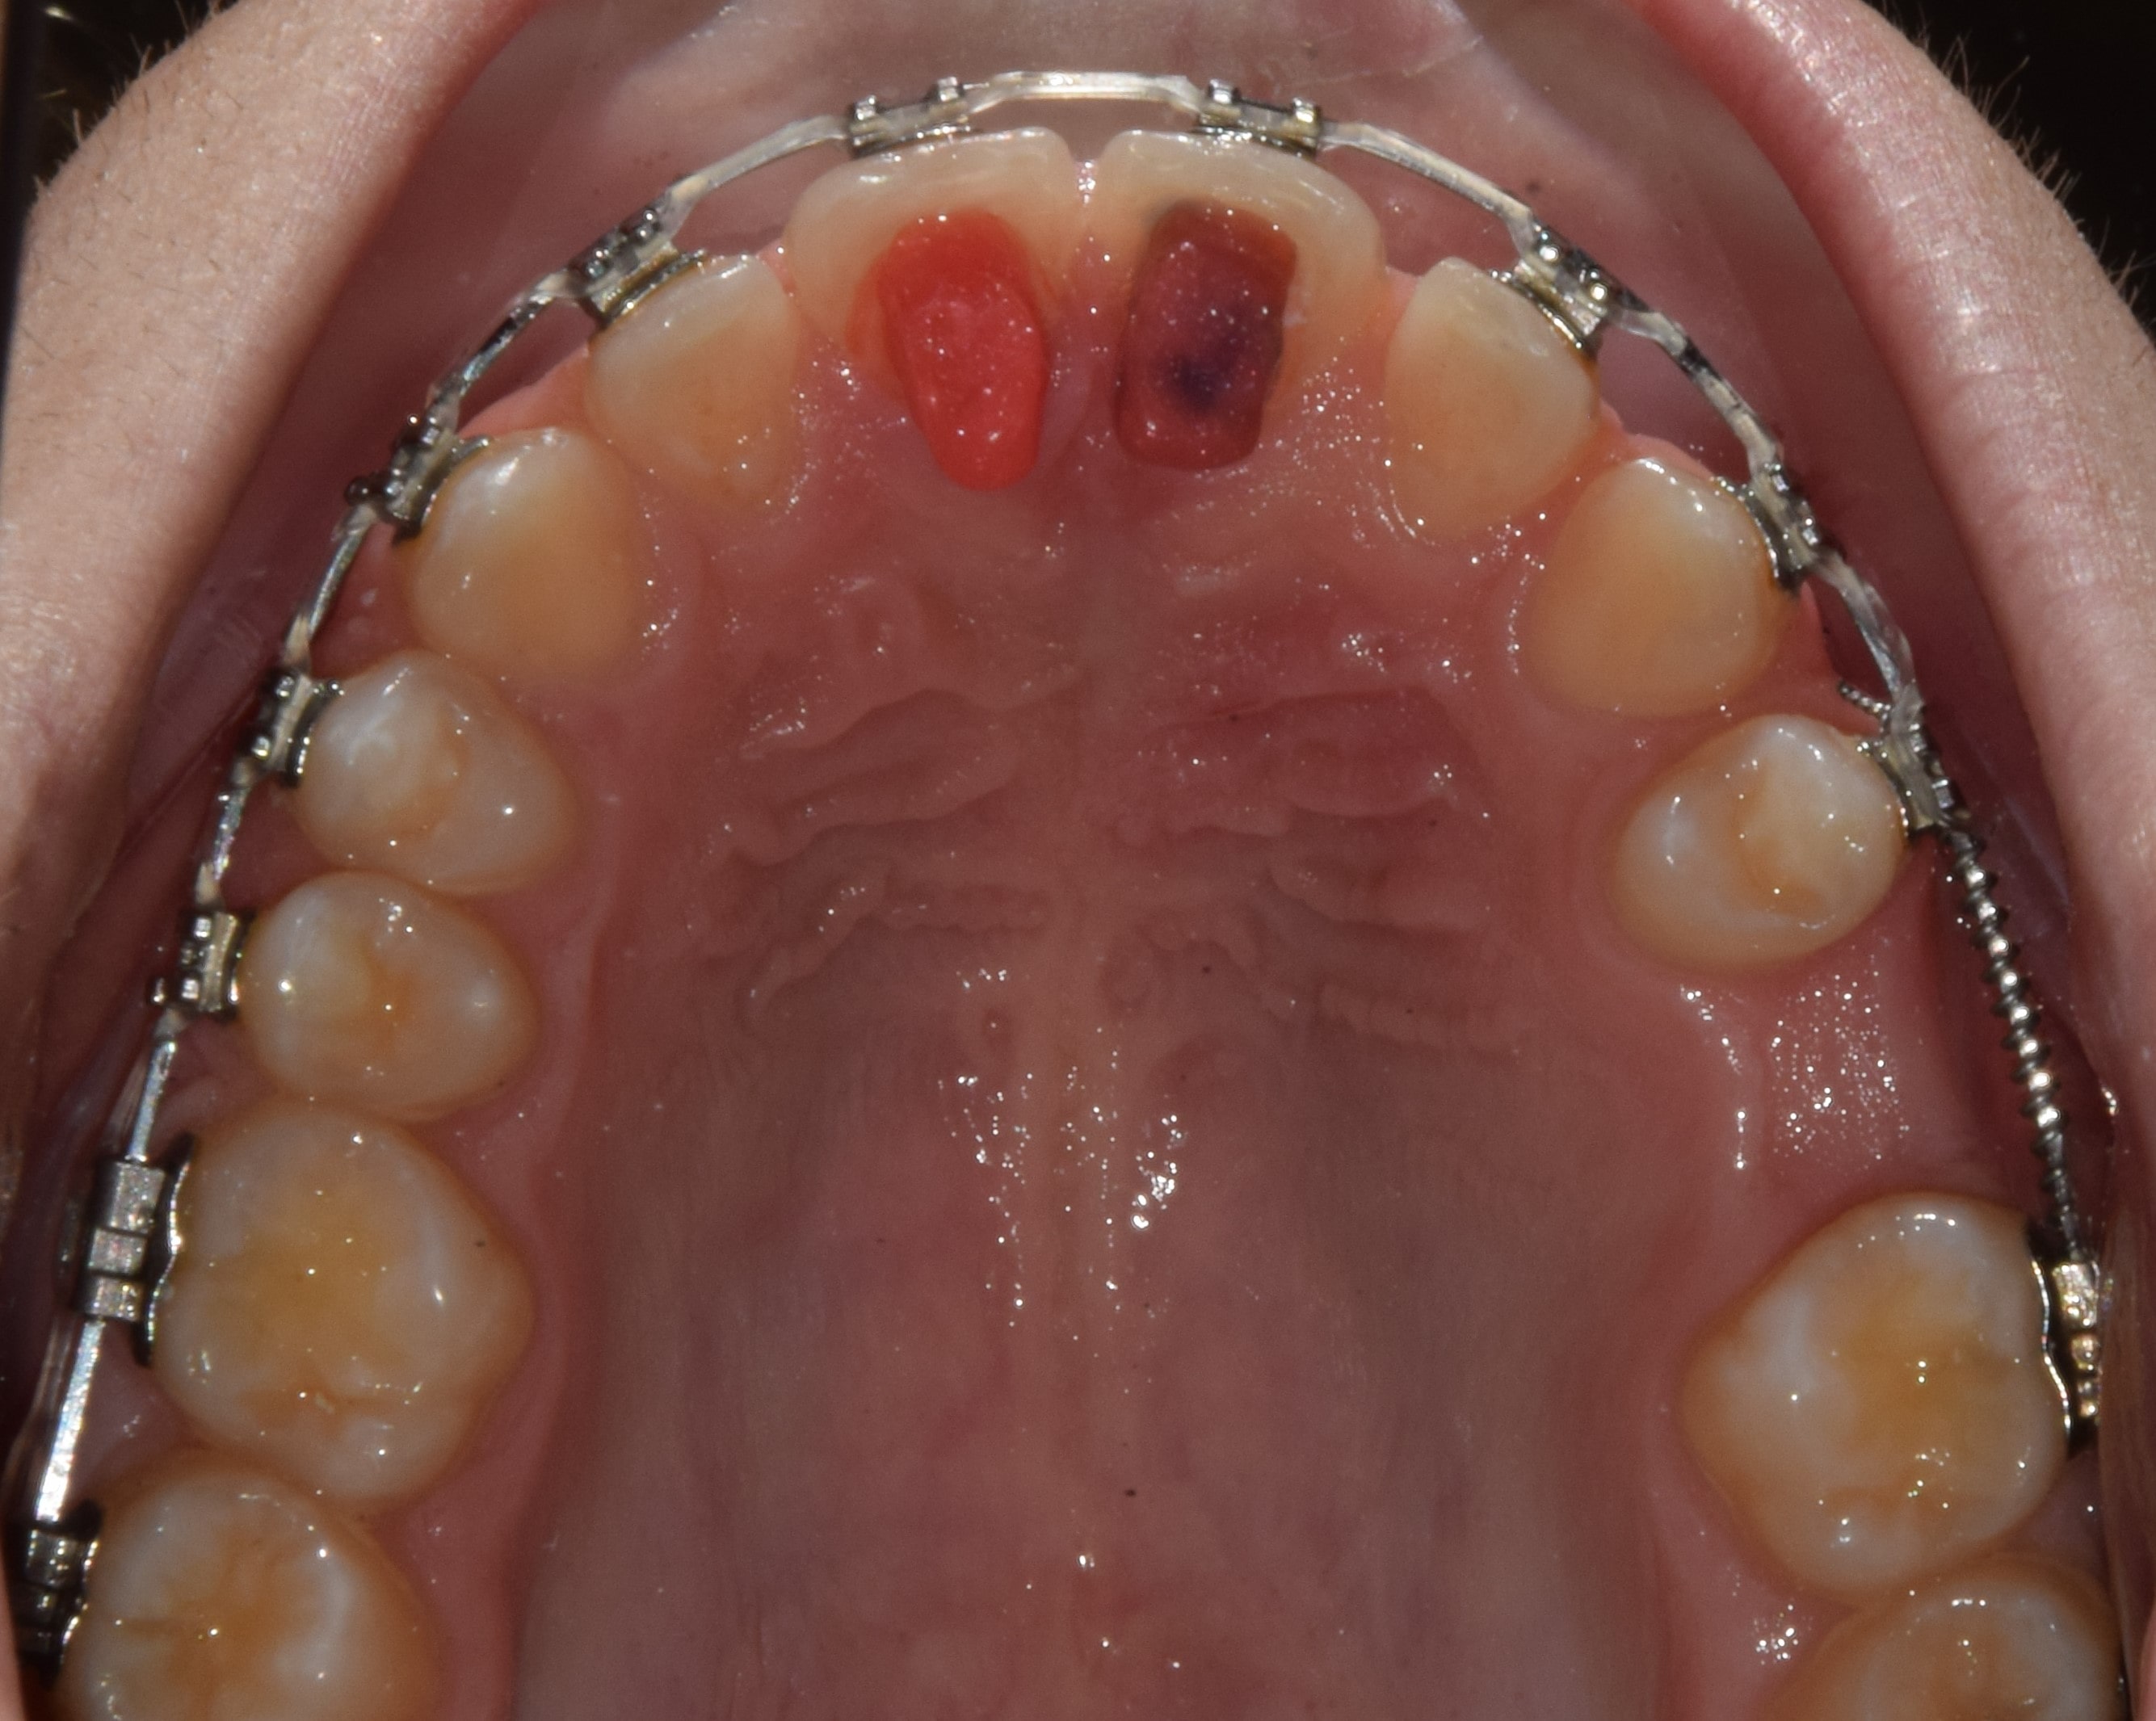

Ajakfék

Az ajakfék nem más, mint az ajkak mozgását szabályozó, korlátozó nyálkahártya tömörülés, mely az alsó és felső első metszők fölött-között helyezkedik el. A túlságosan kifejezett ajakfék beszédproblémát, ínyvisszahúzódást, vagy akár rést is okozhat a metszőfogak között. A köteges, kifejezett ajakféket egy kis szájsebészeti beavatkozás során korrigálni lehet, legkíméletesebben lézerrel.